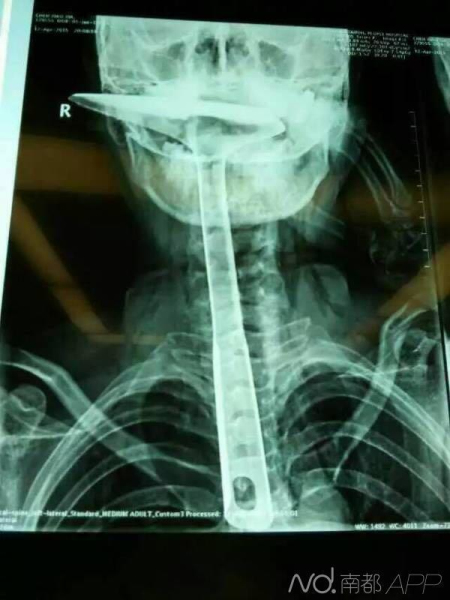

医生也被女子用炒菜铲插进食道的样子惊呆了,炒菜铲长30公分,活生生的插进了食道,只露出铲勺,整个食道严重受损。目前,患者已经做了两期手术,再过两周就要出院了,她25公分的食道已经切除了20公分。

陈女士被带到医院后,拍片显示,整个铁锅铲把手已经在胸里了,病情严重,当晚就被转到了康华医院。医生也被震惊了,总长大概30公分的锅铲手柄整个已经插入食道,食道表皮粘膜损伤严重,且被捅破了一个洞,“而且,手柄已严重挤压到了肺部,导致右肺部已无法正常扩张。”胸腔全是大血管,拔出后有可能会大出血危及生命,当天晚上11点多就对陈女士进行了手术,先将锅铲从食道里面拔出来,由于胸位食道受损严重,只能切除了。

锅铲被取出来了,但是陈女士长25公分的食道被切除了20公分,因为锅铲的手柄很脏,所以还要防止术后感染。第一期手术把命保住了,第二期手术就要解决进食的问题,医生把陈女士的胃部拉伸至颈部,与食管接起来,这是食道癌患者常用的手术方法,康复后就可以正常进食了。要是第一期手术没做好,以后就要将食物从腹部直接注射进小肠了。